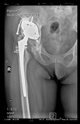

The radiological examination allowed us to verify the close bone-to-implant contact and the unchanged position of the implant during follow-up.

In all the cases operated with the above-described targeting procedure, the stems of the cups remained between the cortical bone surfaces without perforation of the linea terminalis, as shown by postoperative radiographs. There were no complicated surgical situations. In 16 cases, the wound healings were uneventful, and the hips were able to bear weight again after postoperative rehabilitation.